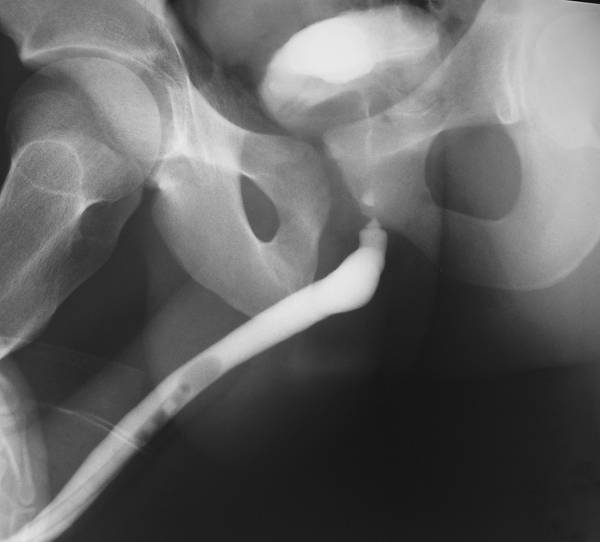

УРЕТРОГРАФИЯ

Уретрография — метод рентгеновского изображения мочеиспускательного канала после заполнения его контрастным веществом. В качестве последнего обычно используют жидкие средства, которые необходимо вводить медленно, осторожно, без большого давления (во избежание уретровенозного рефлюкса). Такую уретрографию называют восходящей или ретроградной. При исследовании мочеиспускательного канала во время восходящей уретрографии можно получить изображение мочевого пузыря. Этот метод называют уретроцистографией.

На восходящей уретрограмме пещеристая часть передней части мочеиспускательного канала представлена в виде полосы с параллельными ровными краями. Луковичная часть мочеиспускательного канала несколько растянута, образует выпуклую книзу дугу. Задняя часть мочеиспускательного канала имеет вид полосы и образует прямой или несколько тупой угол, простираясь до дна мочевого пузыря, тень которого располагается на уровне симфиза или немного выше его.

Для получения хорошего изображения задней мочеиспускательного канала следует предварительно наполнить мочевой пузырь контрастной жидкостью в количестве 200–250 мл и попросить больного помочиться. Во время мочеиспускания (микционная цистоуретрография) выполняют рентгеновский снимок. При этом стенки задней части мочеиспускательного канала хорошо растягиваются, она наполняется контрастной жидкостью, что позволяет получить её отчётливое изображение на снимке. На нисходящей уретрограмме задняя часть мочеиспускательного канала представлена в виде широкой полосы с ровными контурами. Иногда при этом в её средней части виден небольшой, овальной формы дефект наполнения, соответствующий местоположению семенного бугорка. Уретрография позволяет точно установить диаметр просвета различных отделов мочеиспускательного канала и диагностировать патологические изменения в нём. С её помощью удаётся обнаружить следующие аномалии: удвоение мочеиспускательного канала, парауретральные ходы, дивертикулы. Особенно большое значение этот метод исследования приобретает в диагностике сужений мочеиспускательного канала. Он позволяет определить количество стриктур, их расположение, протяжённость, состояние мочеиспускательного канала проксимальнее места сужения, наличие уретральных свищей (рис.).

Стриктура мембранозного отдела мочеиспускательного канала (ретроградная уретроцистограмма).

Стриктуру задней части мочеиспускательного канала считают доказанной лишь при визуализации её сужения на нисходящей уретрограмме.

При опухолях мочеиспускательного канала на уретрограмме наблюдают дефект наполнения с неровными изъеденными контурами.

Восходящая уретрография нашла широкое применение в диагностике повреждений мочеиспускательного канала. Используя уретрографию жидким контрастным веществом при разрывах мочеиспускательного канала, удаётся довольно точно определить характер повреждения органа (проникающий и непроникающий разрывы) и его локализацию. В месте разрыва контрастное вещество проникает за пределы мочеиспускательного канала, затекая в окружающие ткани и образуя тени неправильной формы. При неполных разрывах мочеиспускательного канала контрастное вещество не проникает за её пределы. Иногда удаётся видеть дефекты наполнения неправильной формы (сгустки крови). Уретрографию считают ценным методом диагностики разрывов мочеиспускательного канала, позволяющим выбрать правильную лечебную тактику. В ряде случаев уретрография помогает обнаружить характер поражения простаты. При аденоме задняя часть мочеиспускательного канала удлинена, с ровными контурами, в то время как при раке простаты она имеет неровные изъеденные контуры. При восходящей уретрографии в случае туберкулёзного поражения органа иногда наблюдают проникновение контрастного вещества в ткань простаты. Аналогичная картина возможна и при гнойном воспалении железы после опорожнения абсцесса в мочеиспускательный канал. Эти рентгенологические признаки весьма важны в дифференциальной диагностике заболеваний простаты.